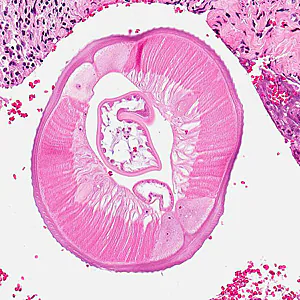

A 55-year-old woman sought medical attention for a nodule on the right side of her head. The patient presented with pain on the right side of her head for the past two months. Two weeks prior to seeking medical attention, she felt a painful 0.5 cm lump on her right temple. The nodule was removed surgically and sent to Pathology for histological testing. Stool and blood specimens were also collected, processed, and examined for parasites with negative results. The nodule was sectioned, stained with hematoxylin and eosin (H&E), and examined microscopically. Images were captured and sent to DPDx for diagnostic assistance. Figure A was captured at 40x; Figure B at 100x; Figures C and D at 200x magnification. What is your diagnosis? Based on what criteria?

Figure B